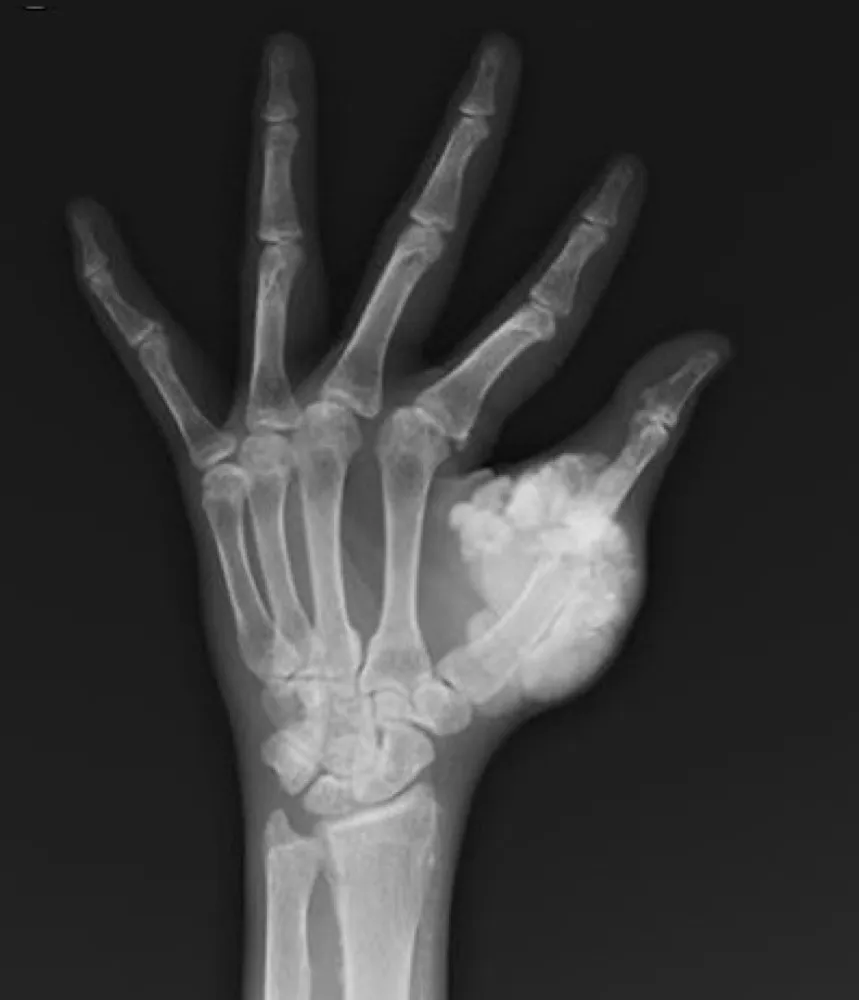

Uma causa incomum de hematúria glomerular intermitente!

Hematúria pós infecção, caso clínicos para auxiliar no entendimento de causas glomerulares comuns e raras...